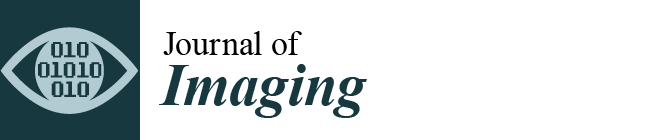

- Anal sphincter complex: This shows variable composition and signal intensity on axial T2-weighted images depending on the level. The upper part consists of the internal sphincter, longitudinal muscle, and puborectal muscle. The middle part features the intersphincteric space, which appears as a high-signal-intensity, slit-like space between the internal sphincter (5 mm thick, intermediate signal intensity) and the external sphincter (1.5 mm thick, low signal intensity). A thin hypointense circular structure within this space represents the longitudinal muscle, which is a continuation of the outer longitudinal smooth muscle of the rectum. The lower part contains the external sphincter and the longitudinal muscle layer. On mid-coronal T2-weighted images, the thicker inner layer is formed by the two halves of the internal sphincter in apposition, while the intersphincteric space is visible as a thin, high-signal-intensity layer. At the outer margin, a cleft divides the puborectalis muscle (above) from the external sphincter (below). On midsagittal T2-weighted MR images, the anal sphincter appears as a low-signal-intensity, homogeneous, cylindrical structure, approximately 4 cm long, composed of muscle layers extending from the attachment of the levator ani muscle to the rectum. Lastly, the perianal spaces are clearly seen as two symmetrical, high-signal-intensity, fat-containing, pyramid-shaped spaces surrounding the hypointense anal canal, with multiple fibrous septa. The apex is visible at the origin of the V-shaped levator ani muscle, along with the supralevator space above it.